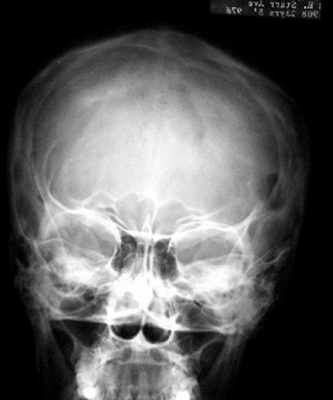

Затем для подтверждения диагноза проводят видеоторакоскопическую биопсию легкого. При данном диагнозе простое проведение бронхофиброскопии с биопсией даст очень мало информации. Чтобы определить степень поражения других органов при гистиоцитозе проводят: рентгенографию скелета и черепа, по показаниям (при подозрении на поражение головного мозга) - магнитнорезонансную томографию (МРТ).

Использование различных методов визуализации (рентгенография, КТ, МРТ) позволяет выявить очаги деструкции величиной до 5 см с четкими границами без склеротических изменений, иногда — патологические переломы, уплощение пораженных позвонков (vertebra plana).